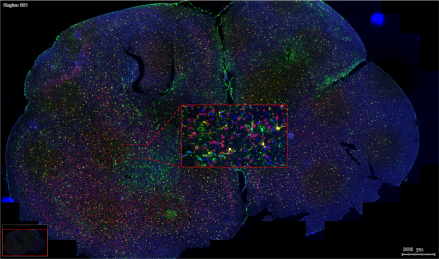

ĪĪĪĪ╗∙ė┌AIūRäeĄ─┐šķg┐╔ęĢ╗»Ż¼īŹ¼F═¼ę╗ÅłŪąŲ¼═Ļ│╔Ė▀Š½£╩Č╚╝Ü░¹ūRäe║═ūįäė╗»ī¦║ĮŪąĖŅŻ╗100%å╬╝Ü░¹╝ēśėŲĘ╩š╝»Ż¼┤_▒ŻČ©ąįČ©┴┐ĮY╣¹Ą─£╩┤_ąįŻ╗Ė▀╔ŅČ╚Ą░░ū┘|ĮMÖz£yĮY╣¹Ż¼0.1 mm2ŪąŲ¼┐╔Öz£y6000+ĘNĄ░░ū┘|ĪŻ

═©▀^ĮY║ŽČÓ╔½├Ōę▀¤╔╣Ō╝╝ągĪó╝ż╣Ō’@╬óŪąĖŅ╝╝ągĪóSISPROTśėŲĘŪ░╠Ä└Ē╝╝ąg║═Ė▀Ęų▒µ┬╩┘|ūV╝╝ągŻ¼īŹ¼Fī”═¼ę╗ÅłŪąŲ¼Ż¼╝╚┐╔▀MąąČÓ╔½├Ōę▀¤╔╣Ō╚Š╔½ś╦ėø╠ž«Éąį╝Ü░¹üå╚║/╣”─▄ģ^ė“Ż¼ėų┐╔ęį═©▀^å╬╝Ü░¹Ęų▒µ┬╩Ą─╝ż╣Ō’@╬óŪąĖŅīó─┐ś╦üå╚║/ģ^ė“ŪąĖŅŽ┬üĒ▀MąąĖ▀╔ŅČ╚Ą░░ū┘|ĮMīWČ©ąįČ©┴┐Ęų╬÷ĪŻ

Ė▀Š½£╩Č╚╝Ü░¹ūRäeŻ║═©▀^ČÓųž├Ōę▀¤╔╣Ō║═AI╦ŃĘ©Ż¼┐╔╠ž«ÉąįĄžūRäeĻ¢ąį╝Ü░¹į┌ĮM┐ŚŪąŲ¼╔ŽĄ─┐šķgĘų▓╝ĪŻ

═©▀^ī”ąĪ╩¾Ųó┼KĄ─FFPEŪąŲ¼▀Mąą├Ōę▀¤╔╣Ō╚Š╔½Ż¼Ęųäeś╦ėøB╝Ü░¹ĪóT╝Ü░¹Ż¼0.1 mm2Š∙ĶbČ©ĄĮ7600+ĘNĄ░░ū┘|Ż¼PCAĘų╬÷▒Ē├„ā╔éĆģ^ė“ėą├„’@▓Ņ«ÉŻ¼ūC├„┐šķg┐╔ęĢ╗»Ą░░ū┘|ĮMīWĘĮ░ĖĄ─ėąą¦ąį║═Ė▀ņ`├¶Č╚ĪŻ